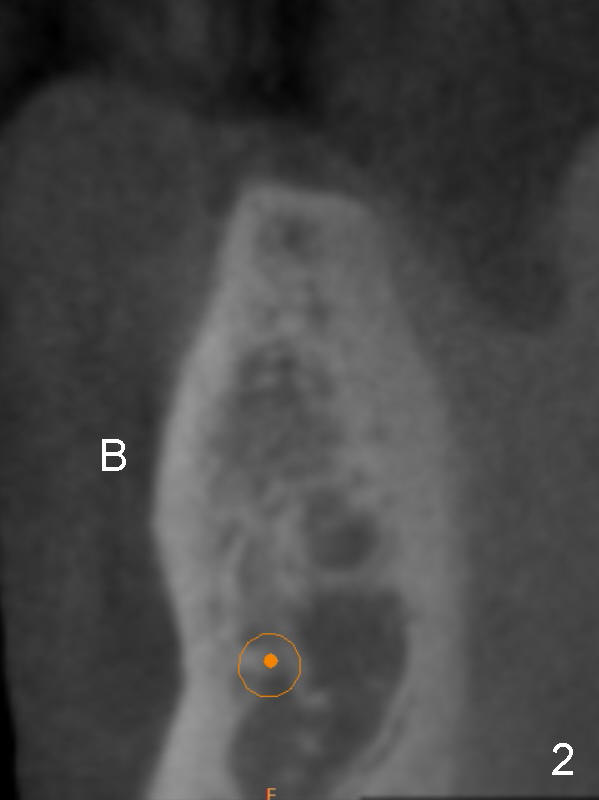

A 75-year-old man requests implant placement at #21 several years after traumatic extraction (Fig.1) with the narrow ridge (Fig.2). After ridge reduction ~ 3.5 mm (Fig.1,3), a 3.5x11 mm implant will be placed to avoid the Incisive canal (In in Fig.1,4) and the Mental Loop (M). In fact the patient agrees to have guided surgery and then changes mind.